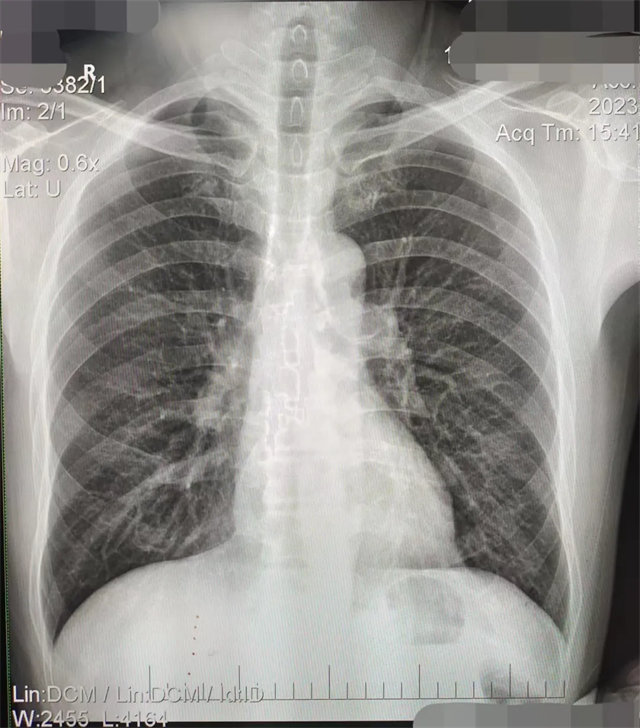

拍攝的不合格胸片的缺陷和解決方法

缺陷:兩肩胛骨未拉開肺野之外,吸氣不完全,且存在金屬飾品遮擋。

解決:去除金屬飾品及內(nèi)衣后重新按標準體位攝片即可。